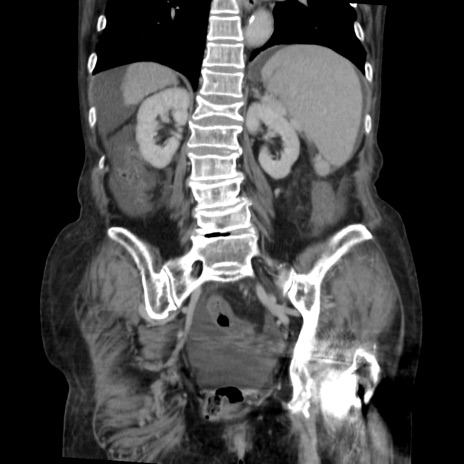

症例31(冠状断像)

【症例】80歳代 女性

【主訴】腹部膨満感

【現病歴】他院にて肝硬変にてフォロー中。1週間前から便秘、腹部膨満感、臍部腫瘤あり受診となる。

【既往歴】肝硬変

【身体所見】腹部膨隆あり、皮膚変化なし、疼痛なし。

【データ】WBC 4600、CRP 0.25